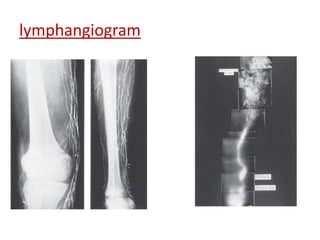

lymphangiogram